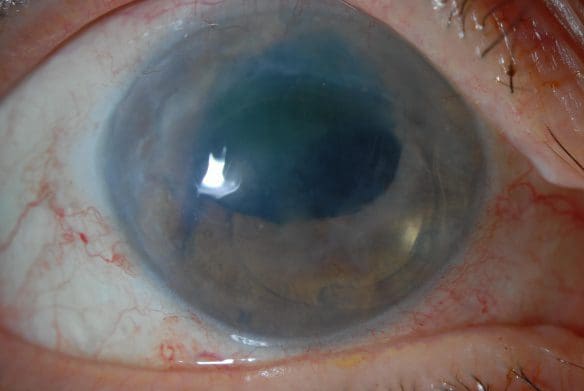

Bullous Keratopathy

Bullous keratopathy is a corneal disease with many different causes. The basic problem is failure of the cornea’s pump cell layer, causing corneal clouding, swelling, and the formation of painful fluid-filled blisters on the surface of the eye.

How can I tell if I have Bullous Keratopathy?

If you’ve had complicated eye surgery, especially glaucoma surgery or cataract surgery, and now you have foggy or cloudy vision, worst in the morning, you may have the disease.